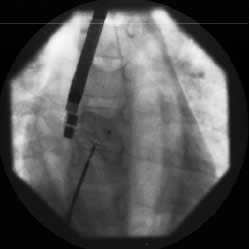

La procedura di impianto viene eseguita in anestesia generale con intubazione del paziente. Un ruolo essenziale, in tutte le fasi della procedura, è svolto dall’ecocardiografia transesofagea. Essa detta le indicazioni alla “fattibilità” (diametro del difetto, misura dei rims settali, ritorni venosi, anatomia atriale), guida l’operatore nel posizionamento della protesi a cavallo del difetto e nel successivo rilascio della stessa, permette una immediata valutazione del risultato (“tenuta” del device dopo rilascio, shunt residuo) (Figure 1, 3, 4). Dall’ottimale utilizzo e dall’esatta interpretazione dei dati forniti dall’ecocardiografia transesofagea dipende in larga parte la riuscita della procedura. Alcuni Autori riportano l’impiego di altri sistemi di monitoraggio durante la procedura quale ad esempio l’ecocardiografia intracavitaria (49). Quest’ultima consentirebbe di evitare l’uso dell’ecocardiografia transesofagea e quindi la necessità dell’intubazione.

Il diametro del difetto, calcolato con “stretched diameter”, variava da 9 a 32 mm (media 17.6 mm) e la misura dei dispositivi utilizzati da 10 a 34 mm (media 18 mm). Tutti i difetti sono stati chiusi utilizzando un singolo device ad eccezione di una paziente con difetti multipli in cui sono stati utilizzati due device di diverso diametro.

A sei mesi di follow up sono stati controllati 31 pazienti. In 30 casi è stata ottenuta la chiusura completa del difetto; in una paziente adulta, nella quale è stato utilizzato un dispositivo di 34 mm, si è verificata l’embolizzazione della protesi in arteria polmonare a 30 minuti circa dalla fine della procedura. L’Amplatzer è stato rimosso dal chirurgo, che ha provveduto, comunque, alla chiusura con patch del difetto interatriale.